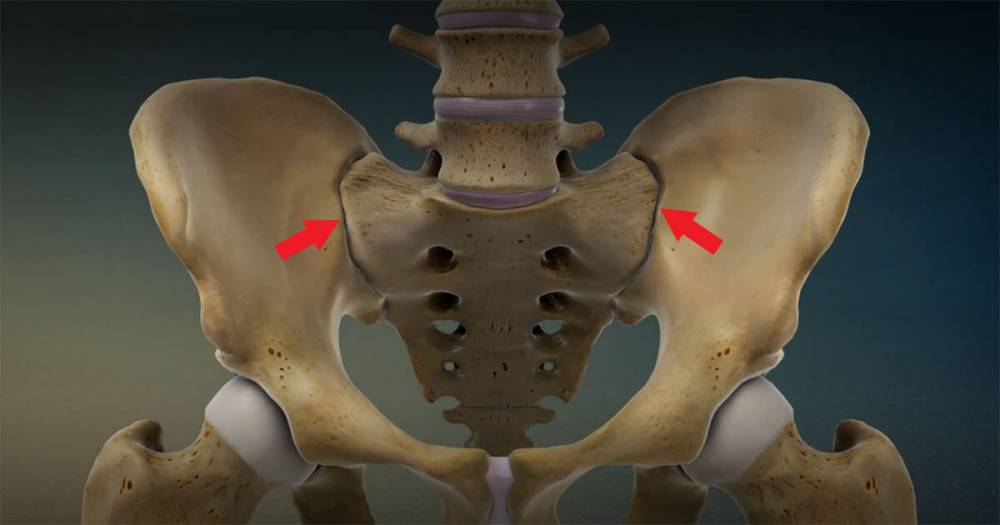

Places to Obtain Autografts

In most cases, many doctors emphasize that it is possible to perform what is known as autografting. This type of procedure depends on choosing the source of the bone graft, which is based on various factors related to size, shape, strength, the ability to stimulate recovery and healing. Some of the prominent places where autografts can be obtained include:

- Pelvic bones.